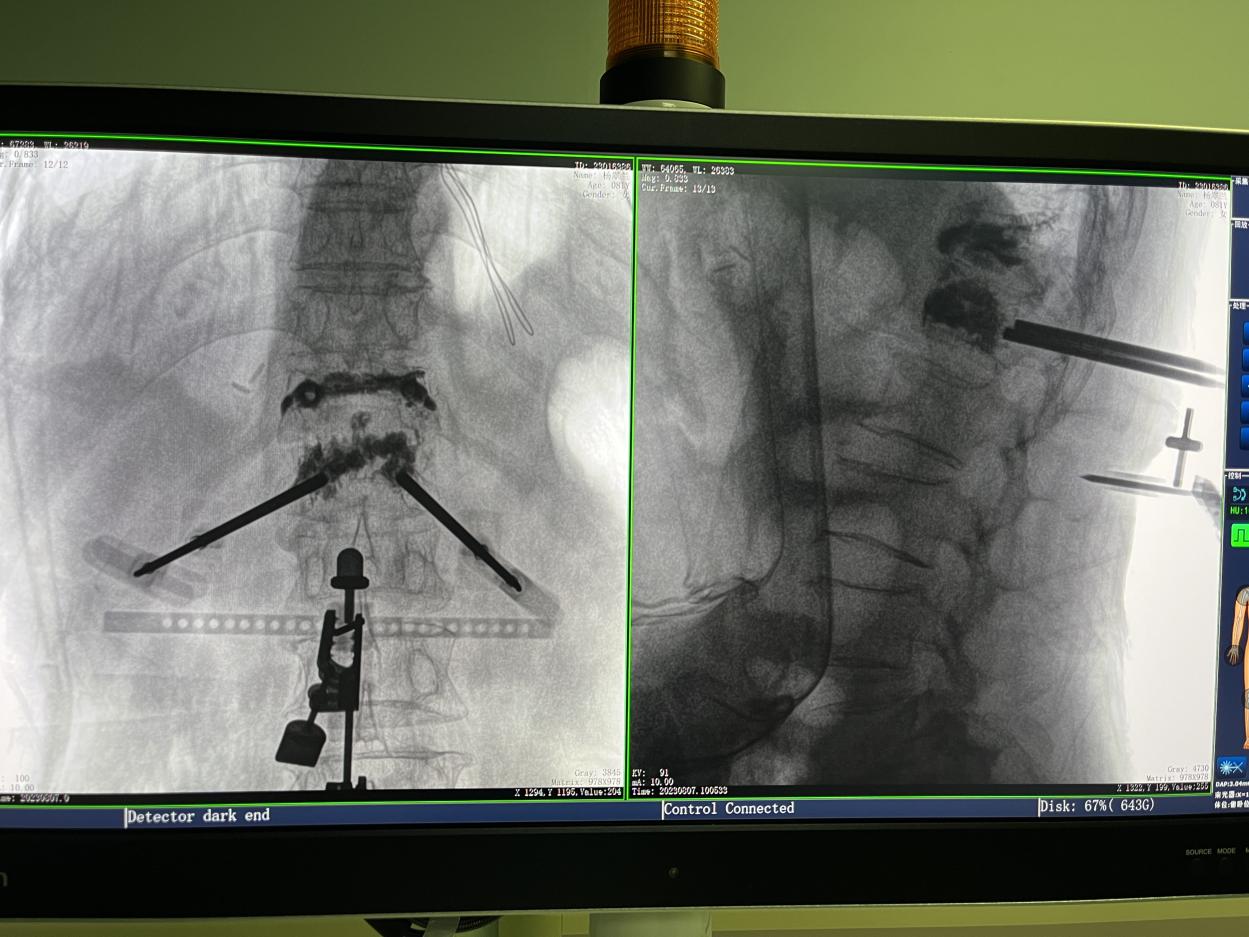

4.微創(chuàng)皮膚切口

傳統(tǒng)的開放式手術(shù)需暴露手術(shù)可見視野,以便醫(yī)生獲得更多的判斷信息,手術(shù)創(chuàng)口大,術(shù)后恢復(fù)時(shí)間長。而在骨科機(jī)器人輔助的微創(chuàng)手術(shù)中,手術(shù)創(chuàng)口僅為1~2厘米左右的小切口,創(chuàng)傷小、恢復(fù)快。

骨科機(jī)器人手術(shù)-術(shù)后影像